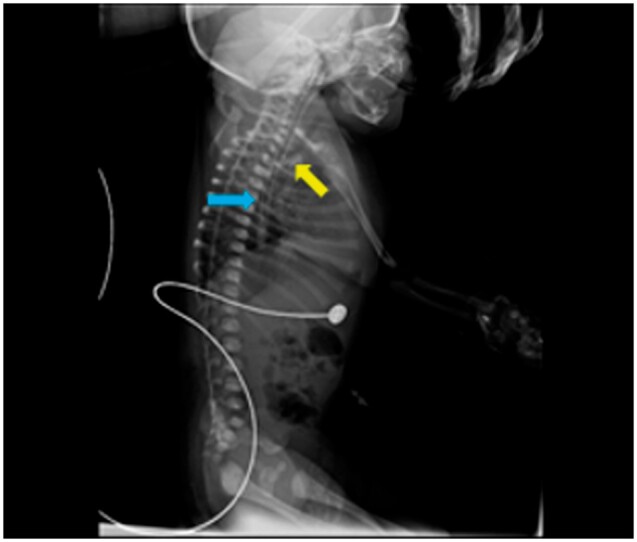

Intramural oesophageal dissection (IED) is an uncommon condition in newborns marked by the separation of the mucosal and submucosal layers of the oesophageal wall, both transversely and longitudinally, which may or may not involve perforation. A neonate presented at 26 h of life with poor respiratory effort and lethargy. She was intubated and was put on mechanical ventilation. Radiograph of the neonate suggested malpositioned endotracheal tube. The fluoroscopic dye-study indicated gastroesophageal oesophageal reflux disease and nothing significant. On limited CT contrast study of thorax, a tubular structure was seen running just parallel to the oesophagus extending from the T2 to the T9 levels. Possibilities of a oesophageal duplication/IED were considered. The neonate underwent an endoscopy and gastrostomy on day of life (DOL) 9. On follow up at 3 months a repeat limited CT study was done with instillation of water-soluble contrast. The previously seen tubular structure running parallel to the oesophagus was no longer seen. This finding suggested a healed IED. This case report emphasizes the significance of multimodality imaging in the diagnosis of this condition.